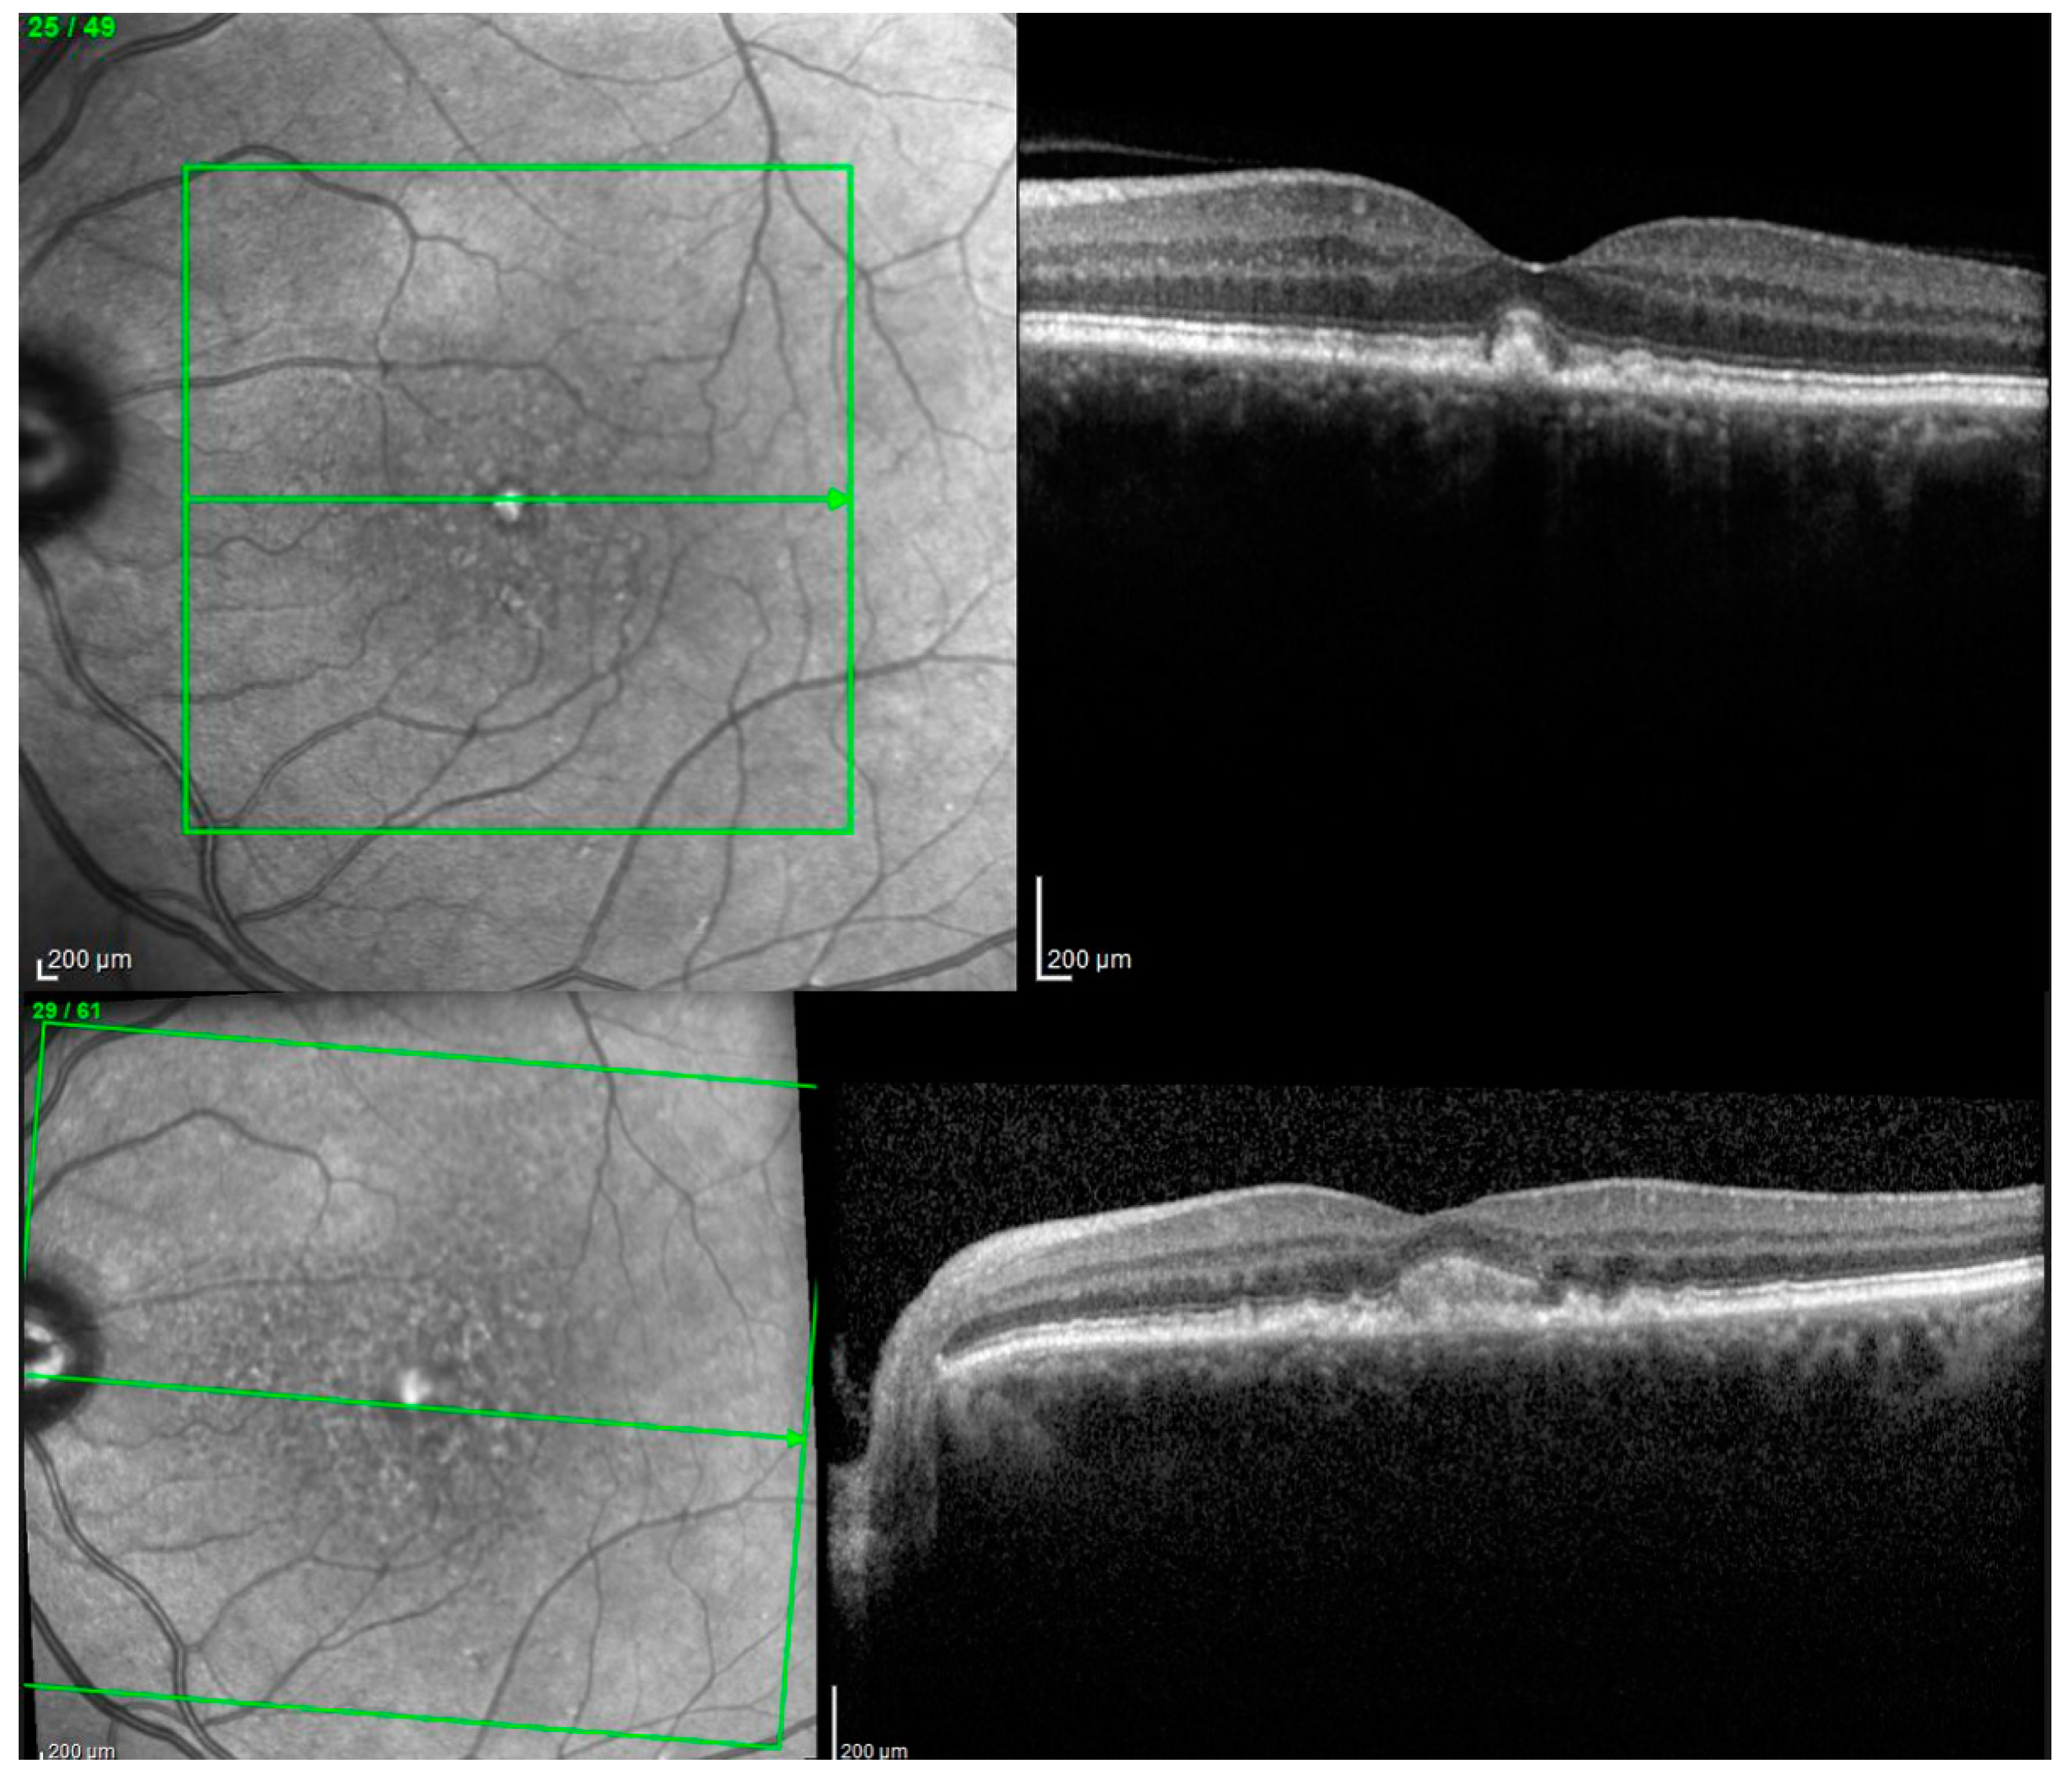

2.3. Spectral Domain-OCT (SD-OCT) Data Aquisition

OCT was performed using a Spectralis OCT (Heidelberg Engineering, Inc. Heidelberg, Germany). All frames were reviewed for the presence of AVL by one of the authors (I.D.). The images were obtained after using the automated eye alignment eye tracking software (TruTrack< Heidelberg, Engineering). Two scanning protocols were used: 1. “Fast macular” scanning protocol: 25 horizontal raster lines per eye separated by 240 µm, centered on the fovea, with a 20 × 20° scan and automatic real mean value (ART value) set at 9, was used; or 2. “Posterior pole” scanning protocol: 61 horizontal raster lines per eye separated by 120 µm, centered on the fovea with a 30 × 25° scan and automatic real mean value (ART value) set at 9. Only images with more than a 20 db signal strength and with individual retinal layers that could be identified were used for the analysis. ETDRS 1 mm macular maps were used to report the macular thickness and the central 1 mm ring was defined as the central thickness.

For 6 eyes with follow-up OCT images and an OCT Q over 20 dB, we collected all the B-scans that passed through the vitelliform lesions. Afterwards, we uploaded the images, one by one in Fiji, and calculated the area for each one of the segmentations (see Figure 3). In order to estimate the volume of the lesion, we summed up all the area measurements/eye and multiplied it with the distance between the sections (120 or 240 µm).

Figure 3. SD-OCT B-scans passing through the entire vitelliform lesion of one clinical study eye.

Biomedicines 11 01382 g003